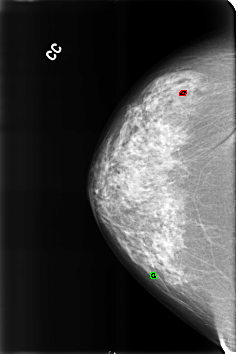

B_3220_1.RIGHT_CC

RIGHT_CC LINES 4592 PIXELS_PER_LINE 3088 BITS_PER_PIXEL 12 RESOLUTION 50 OVERLAY

FILE: B_3220_1.RIGHT_CC.OVERLAY

TOTAL_ABNORMALITIES 2

ABNORMALITY 1

LESION_TYPE CALCIFICATION TYPE LUCENT_CENTER DISTRIBUTION N/A

ASSESSMENT 2

SUBTLETY 5

PATHOLOGY BENIGN_WITHOUT_CALLBACK

TOTAL_OUTLINES 1

BOUNDARY

ABNORMALITY 2